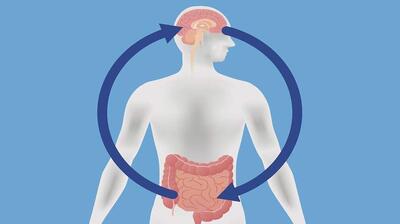

عادت فروکردن انگشت در بینی (رینوتیلکسومانیا) میتواند میکروبهایی وارد حفره بینی کرده و باعث التهاب مغز شود، که با شروع بیماری آلزایمر مرتبط است.